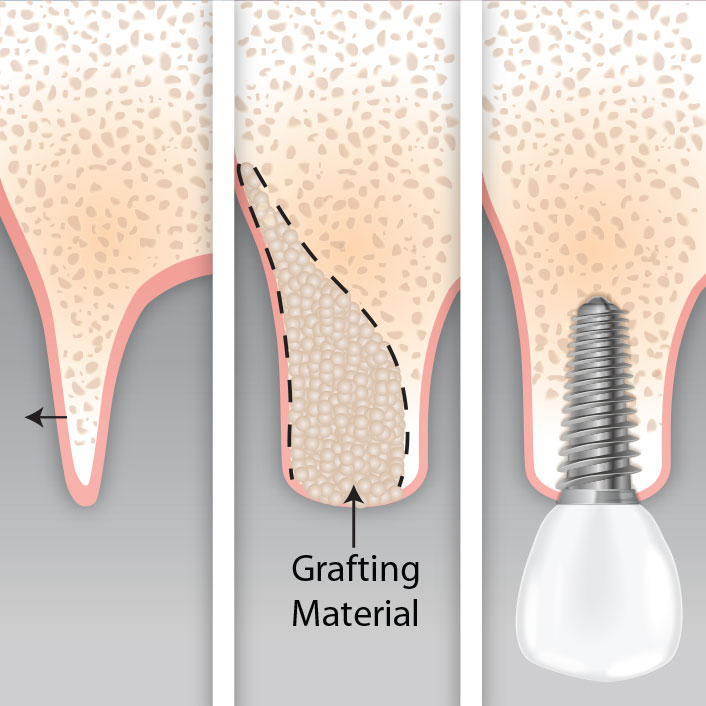

Similarly, if your bite has changed, or if teeth that were previously aligned have drifted apart or developed gaps, periodontal disease may be the cause. This degree of progression requires urgent evaluation — the goal is to preserve the remaining bone and prevent tooth loss.

Early-stage gum disease (gingivitis) can often be managed with a professional cleaning and improved home care. More advanced disease may require scaling and root planing, surgical pocket reduction, or regenerative procedures. The sooner you come in, the more options are available — and the more of your natural teeth we can preserve.